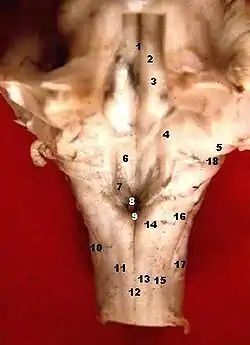

![]() Human caudal brainstem posterior view (Dorsal cochlear nucleus is #5) | |